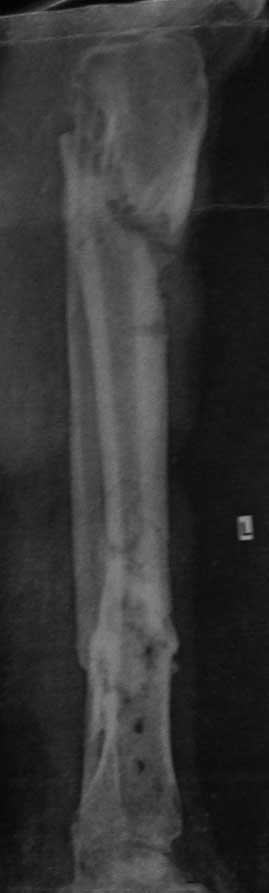

Хронический остеомиелит н/3 б/берцовой кости+атрофичный ложный сустав в/3 б/берцовой кости

Мужчина, 50 лет. Травма в результате ДТП в сентябре 2012 года. Сочетанная травма. ЗЧМТ. Ушиб головного мозга. З/переломы 5-8 ребер справа, пневмогемоторакс. З/двойной перелом обеих костей правой голени

Проводилось оперативное лечение – БИОС б/берцовой кости штифтом, затем КДО аппаратом Илизарова (открылись свищевые ходы на уровне н/3 голени). Впоследствии аппарат Илизарова был заменен на ортез. Больной в январе 2013 года был выписан на амб. долечивание. Через 5 месяцев вновь открылись свищевые ходы. В условиях стационара неоднократно проводилась антибиотикотерапия (достигнуты нестойкие ремиссии), фистулография. На данный момент имеется атрофичный ложный сустав в/3 б/берцовой кости, остеомиелит н/3 б/берцовой кости, свищевая форма. Больной передвигается при помощи костылей с дозированной нагрузкой на ногу в ортезе. На уровне ложного сустава в/3 б/берцовой кости определяется легкая подвижность, в н/3 б/берцовой кости подвижности нет.